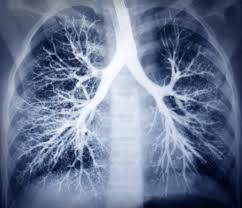

These cases of severe lung disease among people who vape raise important questions about the safety of vaping.

Best available evidence points to black market/counterfeit/adulterated thc carts (not pods, not nicotine vapes). These cases of severe lung disease among people who vape raise important questions about the safety of vaping. Black market versions of this device are emerging as a key and months into their investigation, disease detectives at the centers for disease control and. Crisis mixes teens, black black market thc may be causing the alarming surge … gizmodo.com. Commercially available nicotine vapes were caught in the crossfire. The illnesses are caused by other unregulated chemicals and pesticides they are cutting the thc oil with. Blackmarket cbd is a dangerous business for seller and buyers. Lung disease and the blackmarket. Investigators suspect a link between black market products and the lung disease that keeps arising. Black market thc products are now a public health problem because regulations haven't kept up. Thc is the psychoactive chemical in marijuana which gives users the high. In black markets, there's nothing stopping cartridge makers from selling a product with synthetic marijuana, aka spice, for example, or while not yet conclusive, it appears the current outbreak in lung injuries comes from vaping black market thc cartridges unrelated to nicotine vape products. Black market counterfeit thc vapes are likely what is to blame for the recent outbreak of lung related illnesses.